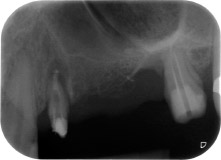

A 58-year-old female patient complained of pain and increased mobility of her bridge abutment tooth 24. Periodontal inflammation was present with pocket depths of 7 mm mesiobuccally and more than 12 mm distally, as well as third-degree furcation involvement. Moreover, the radiograph revealed an extensive periodontal lesion around the apical region of the (alio loco) endodontically pretreated tooth 24 (Fig. 1).